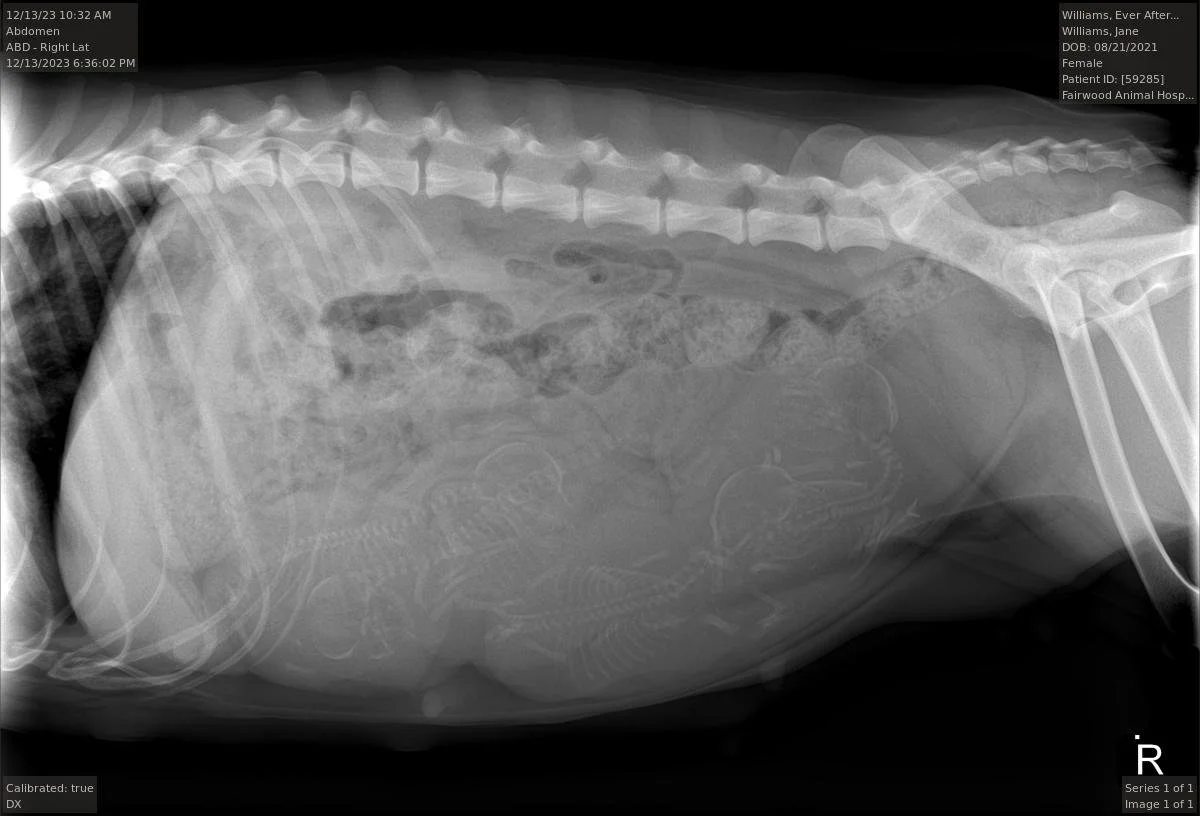

These two were absolutely giddy about their pairing. They had the most playful, joyful honeymoon of all time. The temperaments of their puppies are bound to please us all. How many puppies do you see - 4 or 5?